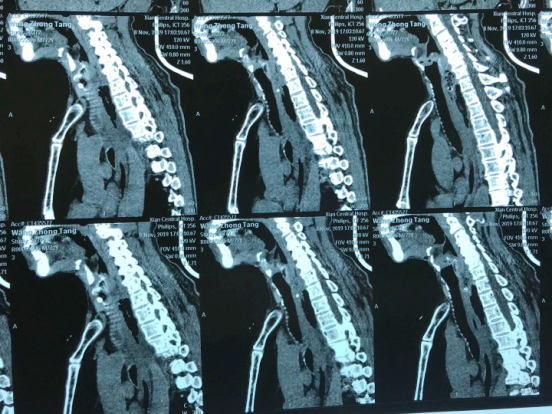

“大夫,快,我这人卡枣核5天没吃饭了,县21点游戏规则 说枣核又往下掉了”,2019118日下午,一位72岁老人在一群家属的搀扶下来到21点玩法研究所 耳鼻喉科门诊,门诊医师刘飞接诊患者询问病史,原来老人在村里“坐席”不慎将枣核误吞,在村卫生室、县城21点游戏规则 等多家医疗机构就诊,未能取出枣核,考虑枣核位置不断下移,建议转上级21点游戏规则 。至此患者因咽痛无法下咽已经5天滴水未进。患者既往糖尿病、冠心病,且未规范药物治疗,基础条件很差。考虑患者病情危重,予以迅速办理入院。权博源主任医师和尹黎波主治医师详细询问病史及查体后,为患者急查血:白细胞22,血糖、血酮、尿酮高,凝血象报危急值。患者食道异物食道穿孔合并严重感染,长期饥饿合并高血糖,手术风险很大。权博源主任医师亲自为患者制定治疗方案,立即抗感染、补液治疗,请内分泌科协助降糖降酮治疗,同时复查CT确定枣核现在位置,指标控制后立即手术。晚上10点,在麻醉科、手术室紧张有序的配合下,终于将枣核和覆盖在上方的鸡蛋样异物取出,术后患者平稳返回病房。